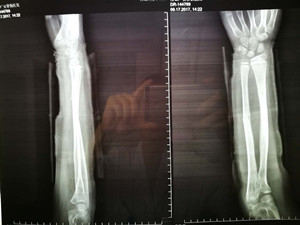

放下電話的虞主任放棄自己這一周僅剩半天的休息時(shí)間,把小女孩接到廣安醫(yī)院。當(dāng)天下午,為小女孩實(shí)施了骨折復(fù)位手術(shù)。術(shù)后,小女孩的骨折復(fù)位十分理想,對(duì)此,病人家屬十分滿意。

(整復(fù)后拍片)